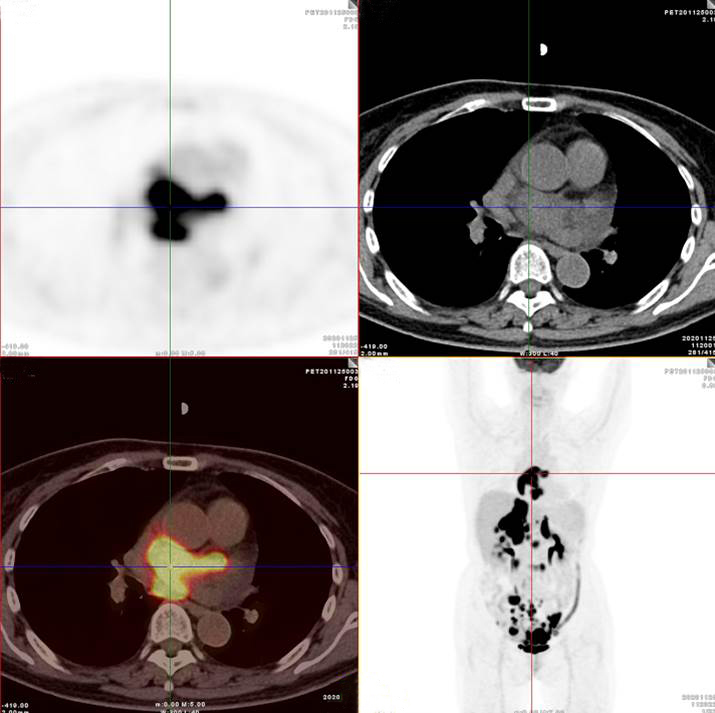

雙側(cè)腎上腺病灶、腹膜后淋巴結(jié)放射性攝取明顯增高

膽囊及雙腎上腺病灶、腹膜后淋巴結(jié)放射性攝取明顯增高